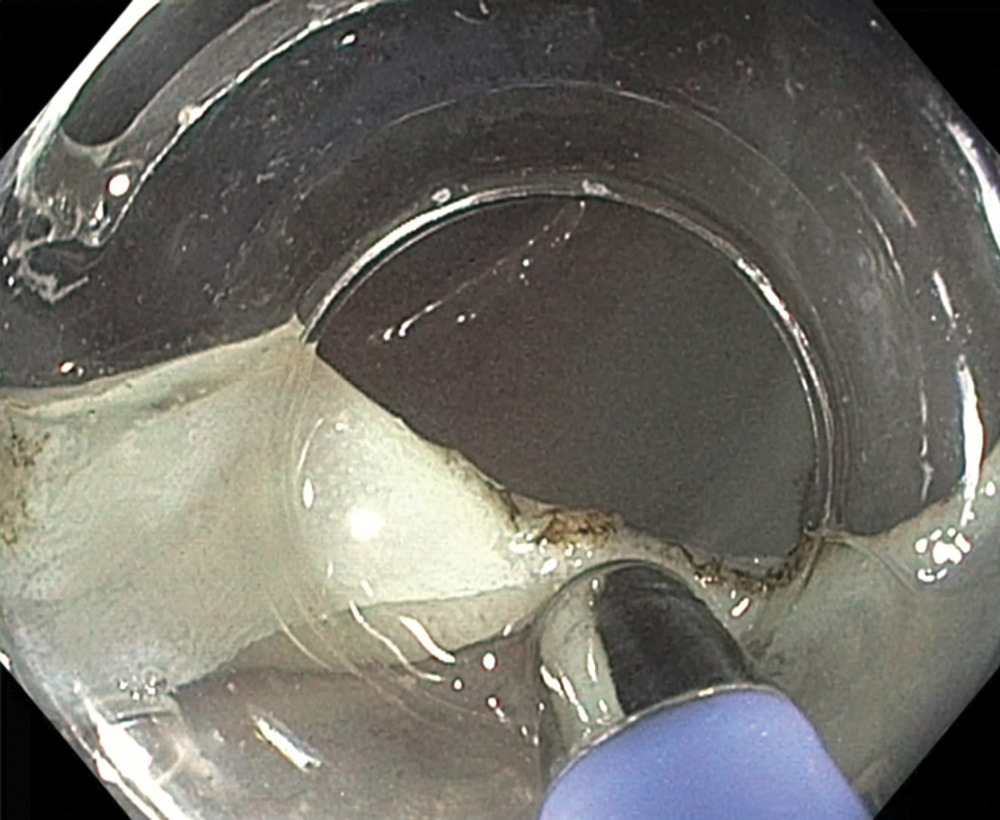

Следующий этап — лечебный. Была выполнена эндоскопическая резекция слизистой оболочки с опухолью с диссекцией в подслизистом слое ESD (рис. 8, 9,